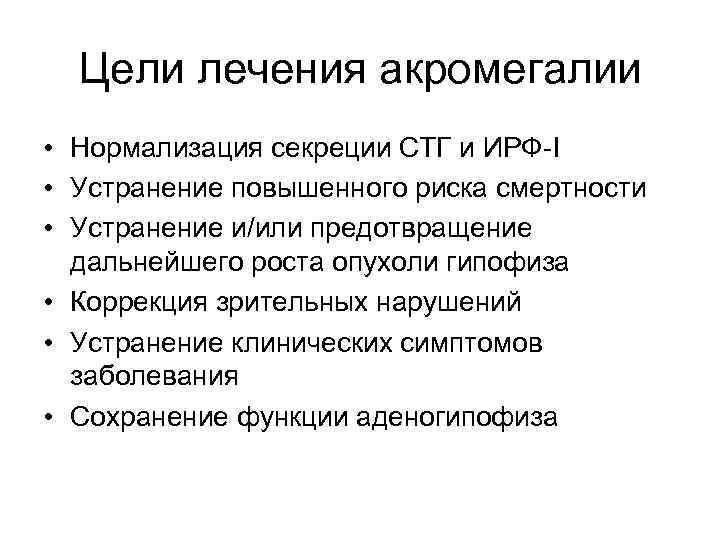

Цели лечения акромегалии • Нормализация секреции СТГ и ИРФ I • Устранение повышенного риска смертности • Устранение и/или предотвращение дальнейшего роста опухоли гипофиза • Коррекция зрительных нарушений • Устранение клинических симптомов заболевания • Сохранение функции аденогипофиза

Цели лечения акромегалии • Нормализация секреции СТГ и ИРФ I • Устранение повышенного риска смертности • Устранение и/или предотвращение дальнейшего роста опухоли гипофиза • Коррекция зрительных нарушений • Устранение клинических симптомов заболевания • Сохранение функции аденогипофиза